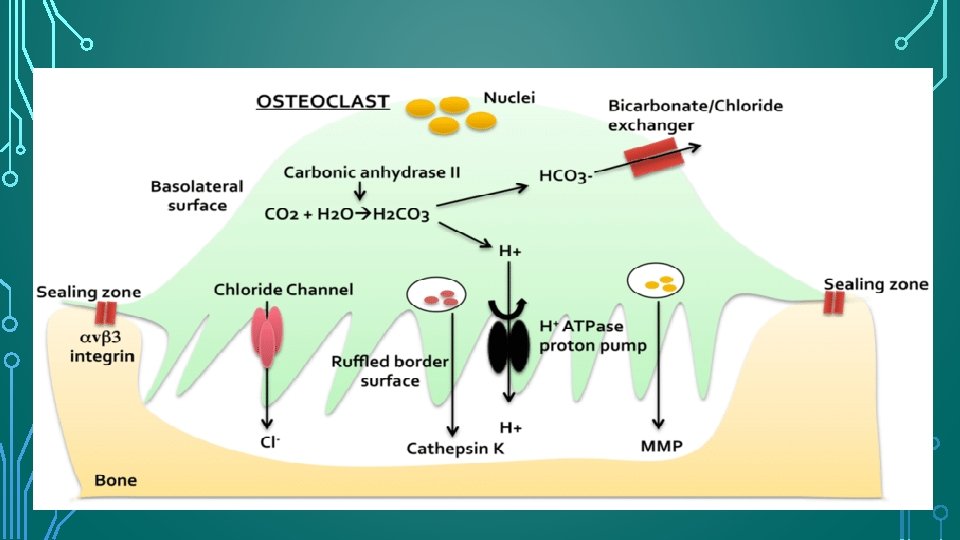

OSTEOCLAST FUNCTION • Osteoclasts are recruited to the site of. injury or irritation by the release of many proinflammatory cytokines. To perform their function, osteoclasts must attach themselves to the bone surface. On contact with mineralized extracellular matrices, osteoclast produces an organelle-free zone of sealing cytoplasm (clear zone) to achieve intimate contact with the hard tissue surface. • The clear zone surrounds a series of fingerlike projections (podosomes) of cell membrane, known as the ruffled border, beneath which bone resorption occurs. The resorptive area within the clear zone, therefore, is isolated from the extracellular environment, creating an acidic microenvironment for the resorption of hard tissues

ODONTOCLAST FUNCTION • Odontoclasts differ from osteoclasts in that they are smaller, have fewer nuclei, and have smaller sealing zones. • Odontoclasts and osteoclasts are functionally similar, have similar enzymatic properties, show similar cytologic features, and create resorption depressions, termed Howship lacunae.

PROPERTY OF CLASTIC CELLS Osteoclasts and odontoclasts do not adhere to non-mineralized collagen matrices.

MOLECULAR SIGNALING • the OPG/RANKL/ RANK transcription factor system that controls clastic functions during bone remodeling has also been identified in root resorption. • OPG- osteoprotegrin- prevents binding of RANKL to RANK- prevents activation of osteoclasts • RANKL: receptor activator of NF-κb ligand : responsible for activation of osteoclasts after binding to RANK on the surface of their precursors • RANK: present on the surface of osteoclastic precursors.